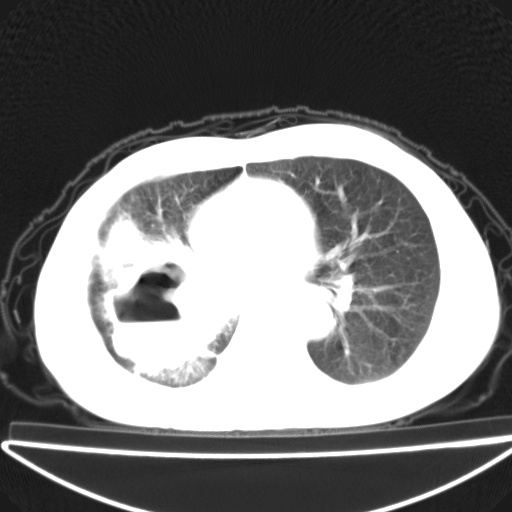

以下是引用jsgdoctor在2008-11-6 22:12:00的发言:[br]右主支气管壁明显增厚,管腔狭窄.考虑为右侧中央型肺癌伴阻塞性炎症\\肺脓肿.

以下是引用zjzjr在2008-11-6 20:25:00的发言:[br]中心型肺ca,合并阻塞性肺炎

以下是引用zsl6918在2008-11-6 19:43:00的发言:[br]右侧中心性肺癌(鳞癌)